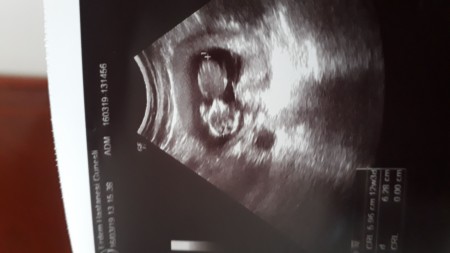

Bugunki görüntümüz gordugumde bir yukari bir aşağıya cok hareketliydi masalalahhx

Gebelik haftası 12+3

Masalllahhh küçücük birde sırtını dönüyor :D

Evet normalde duz olmasi lazim degillmi benimde dikaktmi cekto

Aynen normalde hep yan yatıyor gibi duruyorlar di senin bebiş yüzünü göstermemiş  :D

O asadaki siyah sey ne canm miyomun varmı

Kist olabilir